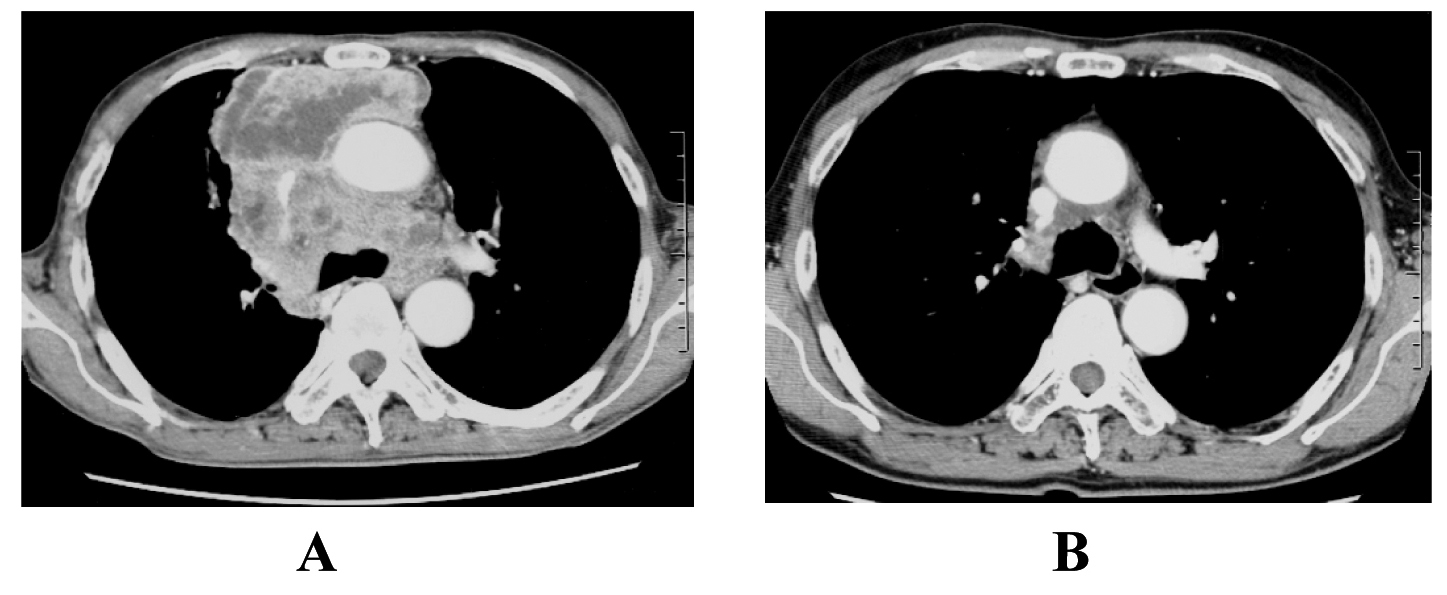

A 65-year-old man was admitted to our hospital because of face edema, general fatigue and appetite loss in July 2002. Chest X-ray and chest CT scan revealed an anterior mediastinal mass (Fig. 3A). After histological diagnosis of thymic carcinoma (squamous cell carcinoma) by percutaneous CT-guided biopsy, he was treated with 5 cycles of ADOC chemotherapy. Good partial response was observed (Fig. 3B). In April 2011, he presented supra vena cava syndrome again. CT scan indicated a mediastinal mass (Fig. 4A). Bronchoscopic examination was performed and transbronchial needle biopsy revealed recurrence of thymic cancer. Readministration of ADOC was initiated in August 2011. After one cycle of ADOC chemotherapy, chest CT scan revealed a partial response (Fig. 4B). However, the patient developed febrile neutropenia and bacterial pneumonia during the first cycle of chemotherapy. He refused subsequent chemotherapy and is currently under observation without symptoms.

![]() Click for large image | Figure 3. The response to initial ADOC chemotherapy in case 2. Chest computed tomography before initial ADOC chemotherapy (A) and after five cycles of initial ADOC chemotherapy (B). |